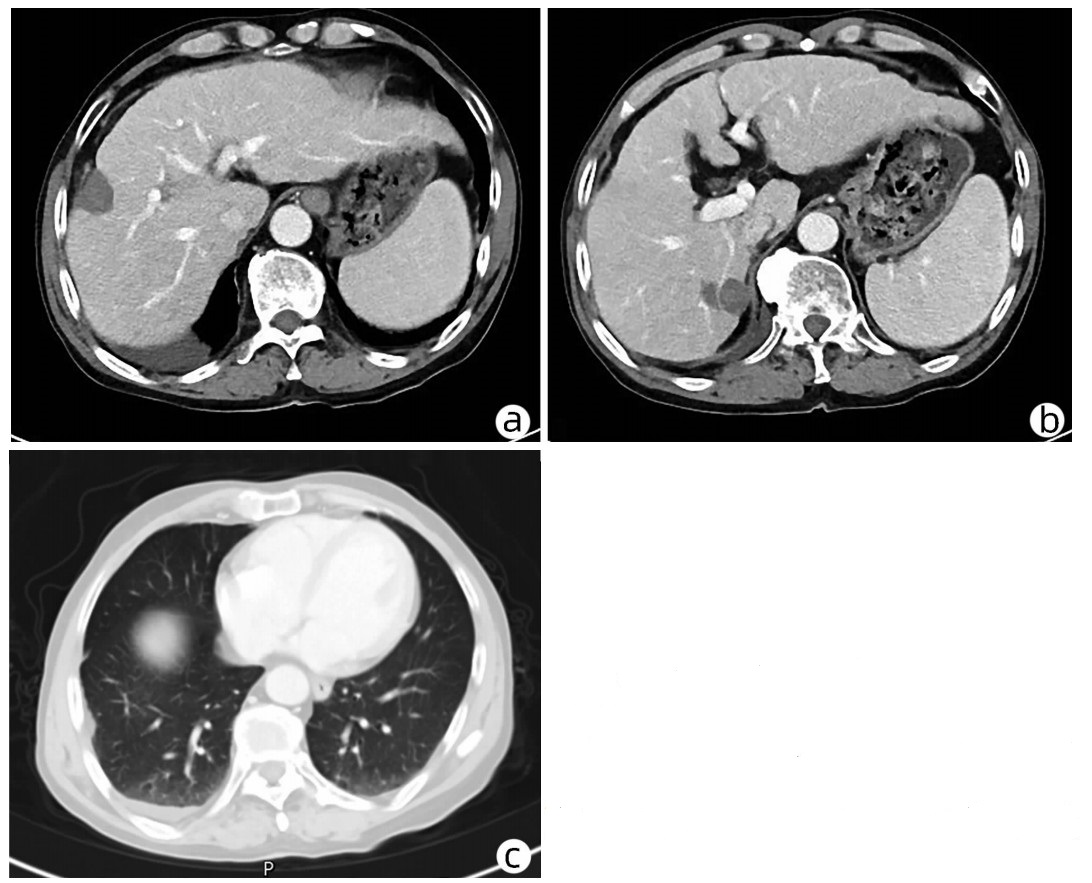

Late-onset diaphragmatic hernia after microwave ablation of hepatocellular carcinoma: A case report

Xiaodong WANG, Yurong ZHANG, Xiaoning ZHU, Ding ZHENG, Jing WANG

2022, 38(8): 1875-1877. DOI: 10.3969/j.issn.1001-5256.2022.08.029

Abstract(895) HTML (335) PDF (2572KB)(68)

Abstract: